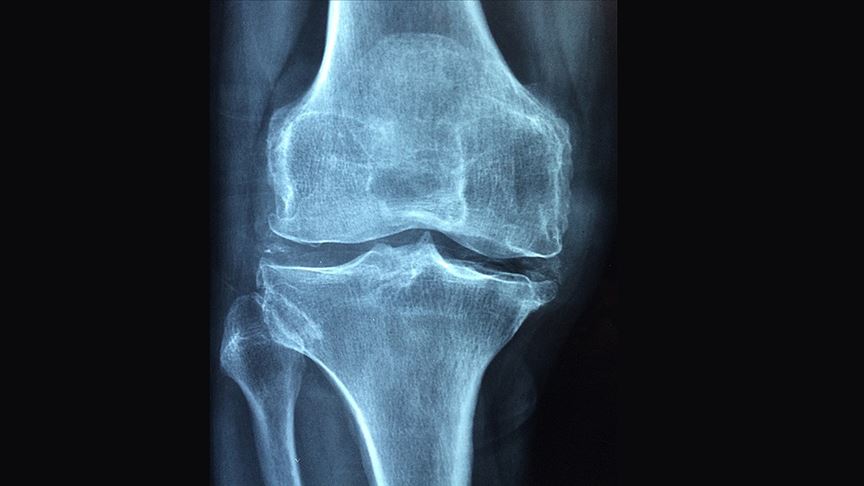

Osteoporozun, kemikleri zayıf ve kırılgan hale getiren bir hastalık olduğunu belirten Kutsal, “Bu durum, küçük bir düşme veya çarpmadan sonra bile kemik kırılma riskini önemli ölçüde artırır. Hastalığın belirgin bir belirtisi olmadığından birçok kişi ancak bir kırık meydana geldiğinde osteoporoz hastası olduğunu fark eder.” ifadelerini kullandı.

Osteoporoza bağlı kırıkların, kronik ağrı ve sakatlık, bağımsızlık kaybı, yeni kırık riskinde artış ve erken ölüm gibi yaşamı tehdit edebilen sorunlara yol açabildiğine dikkati çeken Kutsal, osteoporoz ve ilişkili kırıkların, hastaların yanı sıra aileleri ve toplumu da etkilediğine, sağlık sistemlerini de ağır ve maliyetli yükün altına koyduğuna işaret etti.